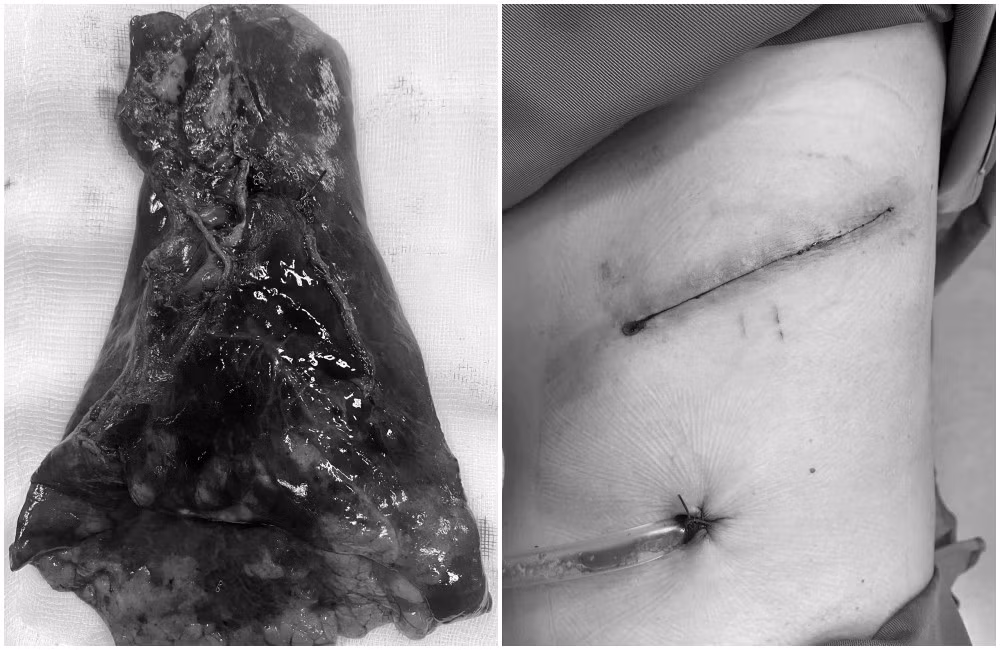

Thuỳ dưới phổi trái chứa khối u ác tính được phẫu thuật cắt bỏ thành công - Ảnh BVCC

Ca phẫu thuật do kíp bác sĩ khoa Ung bướu phối hợp cùng khoa Gây mê hồi sức thực hiện. Sau khi gây mê với thông khí một phổi, kíp phẫu thuật tiến hành rạch những đường nhỏ trên thành ngực và đưa dụng cụ nội soi vào kiểm tra. Quan sát thấy khối u tại thùy dưới phổi trái, kích thước khoảng 16mm, mật độ chắc, xung quanh có hạch mềm.

Sau khi đánh giá toàn bộ tổn thương, các bác sĩ tiến hành cắt các động mạch, tĩnh mạch và phế quản thùy dưới phổi trái bằng máy khâu- cắt (stapler) chuyên dụng. Khối u thùy dưới phổi trái kèm hạch được lấy ra qua đường nội soi và gửi làm giải phẫu bệnh. Kết quả xác định đây là ung thư thùy dưới phổi trái giai đoạn sớm. Quá trình nở phổi kiểm tra diện cắt không phát hiện rò khí.

Sau khoảng 2 tiếng phẫu thuật, kíp mổ đã cắt bỏ thành công thuỳ dưới phổi trái chứa khối u ác tính, bệnh nhân mất máu ít nhờ kỹ năng phẫu tích tỉ mỉ, khéo léo. Sau mổ một ngày, bệnh nhân đã ổn định, tự thở tốt, ngồi dậy do vết mổ nhỏ thành ngực ít đau, hồi phục nhanh.